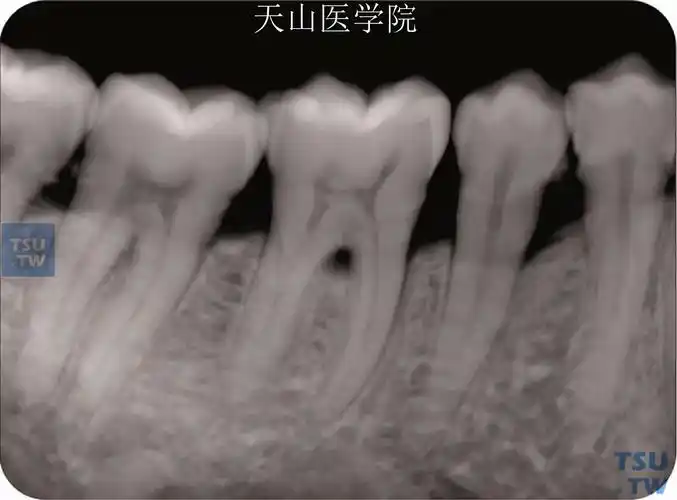

口解下颌第一磨牙解剖要点笔记

下颌第一磨牙指向颊侧的沟状根尖,x线片上不明显